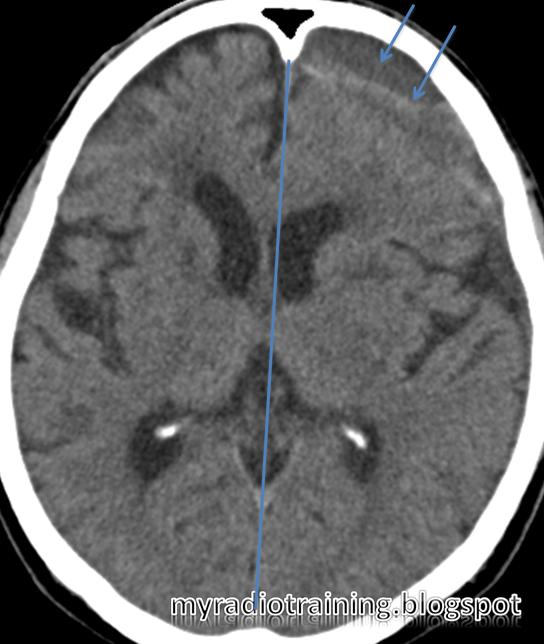

-A, Focal hypodensity in right corona radiata on enhanced ...

Acute infarction | Image | Radiopaedia.org